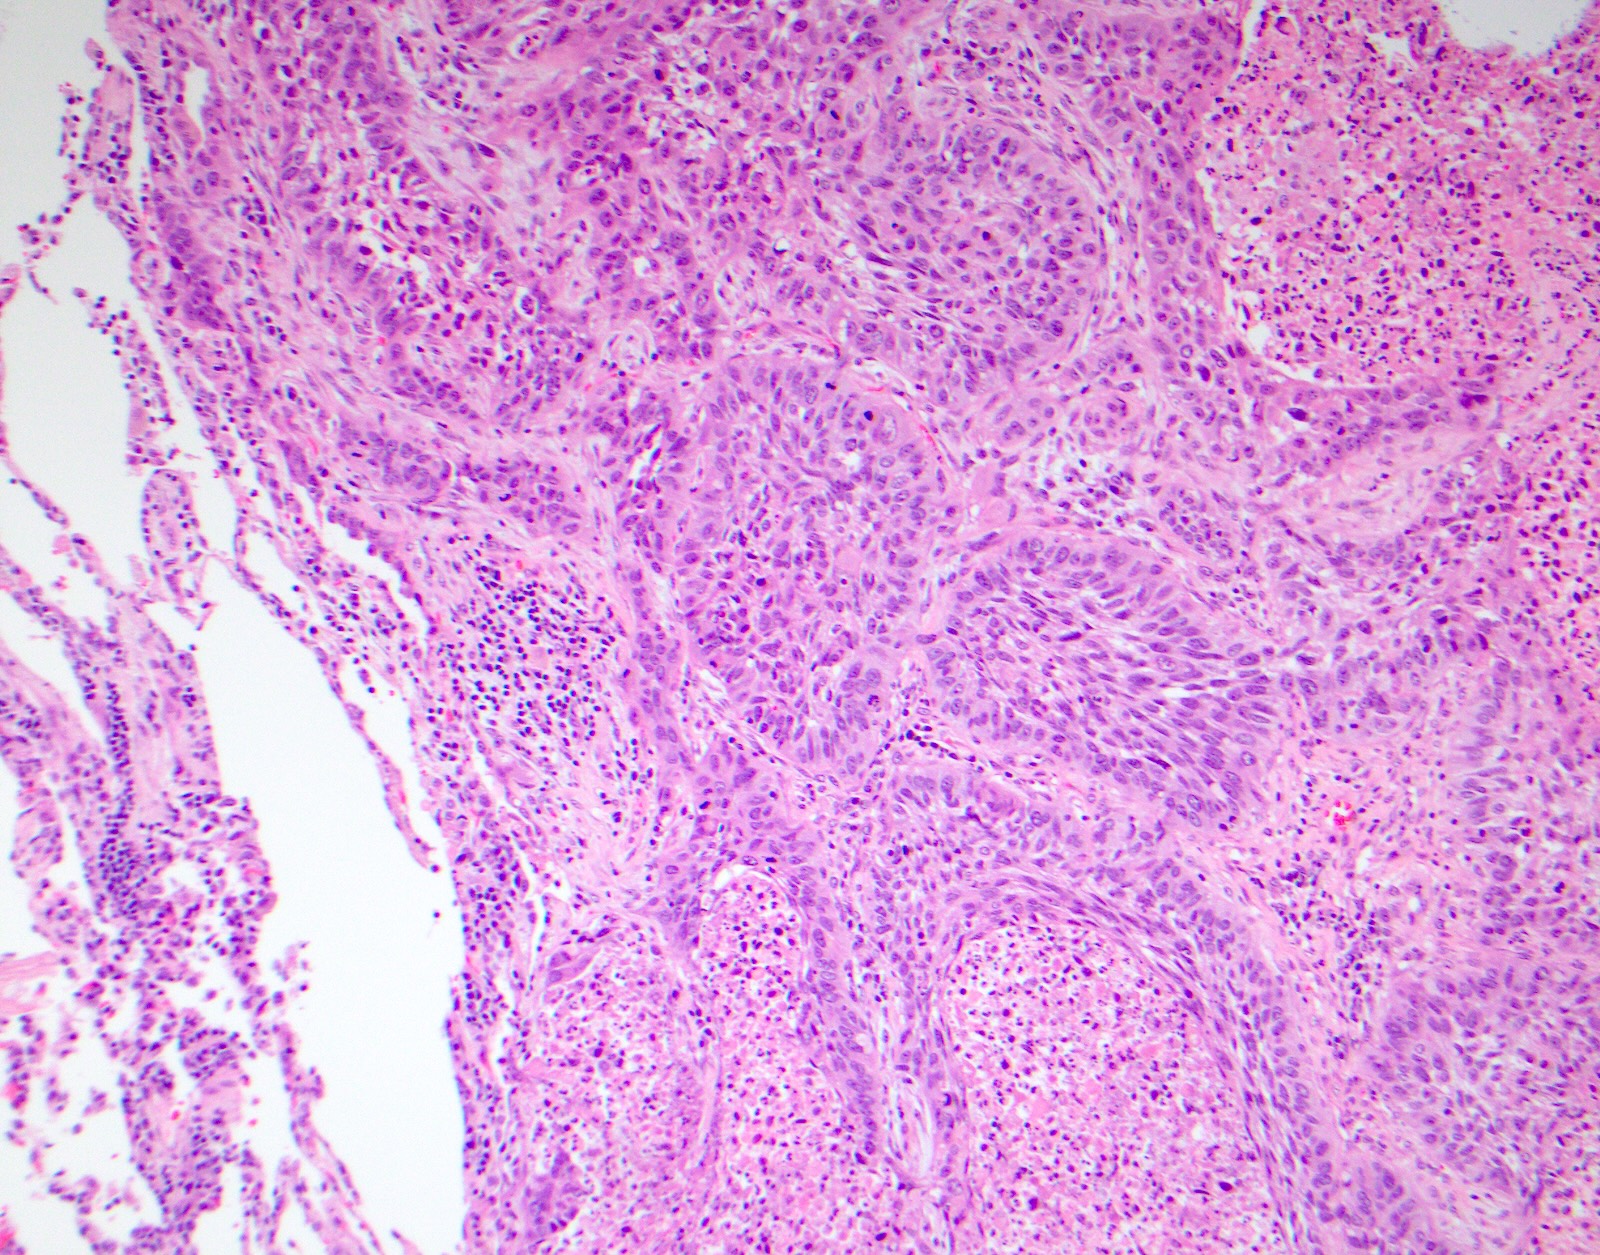

Microscopic (histologic) images

Contributed by Surekha Bantumilli, M.D. and Dimitri G. Trembath, M.D., Ph.D.

- Identification of the basal cell layer in prostate tissue in the determination of carcinoma

Practice question #1

A 65 year old man presents with elevated prostate specific antigen (PSA) and undergoes a prostate biopsy, stained with high molecular weight cytokeratin (HMWCK) (shown above). What is the most likely interpretation of this staining pattern?

Practice answer #1

A. Benign prostate tissue. The basal layer of benign prostate glands will stain with high molecular weight cytokeratin. Answer D is incorrect because staining will be lost on prostatic adenocarcinoma. Answer C is incorrect because high molecular weight cytokeratin staining can be present in high grade prostatic intraepithelial neoplasia but is not diagnostic by itself for this entity. Answers B and E are incorrect because the glandular appearance outlined by the high molecular weight cytokeratin staining is not consistent with either seminal vesicle or urothelial carcinoma.